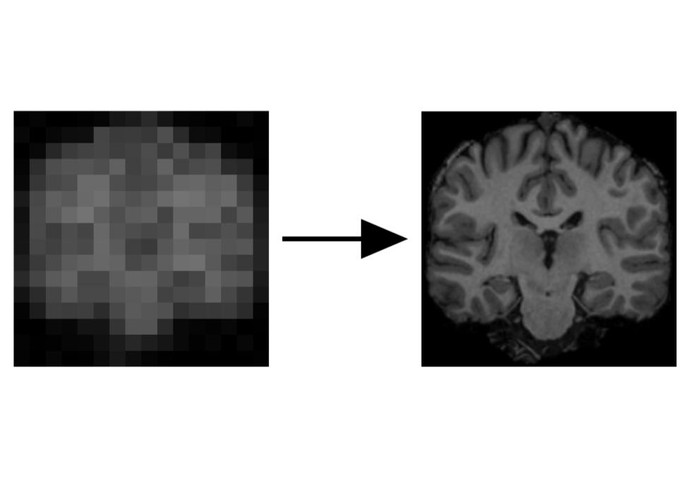

We use techniques from ML, compressed sensing and Bayes’ theorem to improve the quality, speed or cost of medical scans.

We can tackle many different data modalities (brain MRIs, PET, CT, …), chest X-rays, any many more. Such techniques can correct scanning artefacts, motion of patients in the scanner, re-construct from 2D to 3D, and recontruct undersampled MRI which only measure a few points in k-space.

We also use Bayesian techniques such as MCMC or Variational Inference to learn a distribution over the space of potential solutions, this is highly important for such ill-posed problems.